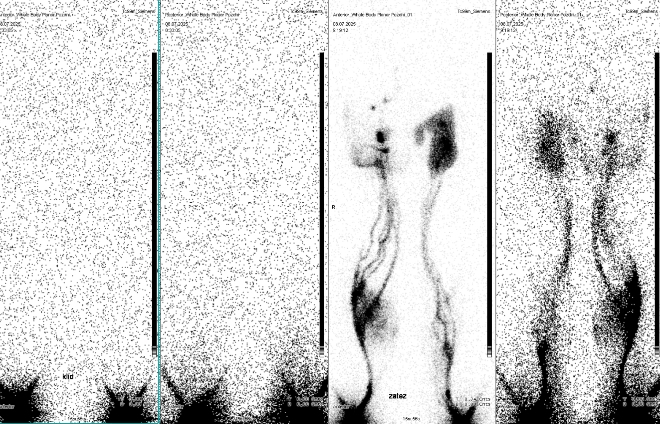

/ Obr. č. 1: Celotělová scintigrafie – vyšetření v klidu a po zátěži.

Po klidu nejsou vůbec patrné kolektory, radioindikátor je pouze v místě vpichů.

Po zátěži zobrazeny kolektory na bércích a stehně, je výrazný reflux do podkoží pravého bérce, proximální části levého stehna, méně výrazně i proximální části pravého stehna (což potvrzuje i SPECT/C). Na levém bérci štěpení kolektoru, na pravém stehně výrazné štěpení kolektorů, všechny probíhají povrchovou cestou – nezasahují do hlubokého systému. V levém třísle v oblasti refluxu je dle SPECT/CT patrná ojedinělá tříselná uzlina, vpravo zobrazeny tři tříselné uzliny a tři uzliny iliakální.

Těžce patologický nález - výrazné funkční a anatomické změny lymfatického systému dolních končetin, jistě v důsledku operačního výkonu